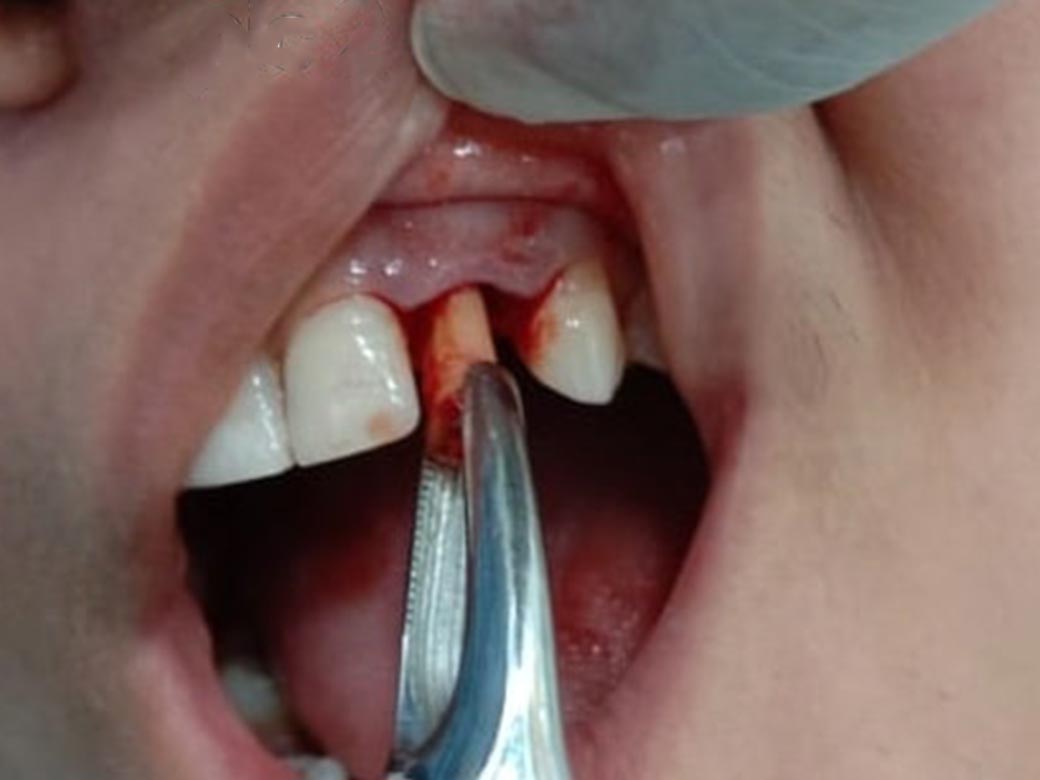

Step 2 : Root piece removed under LA without pain.

Step 3 : Implant measurement compared with root piece.